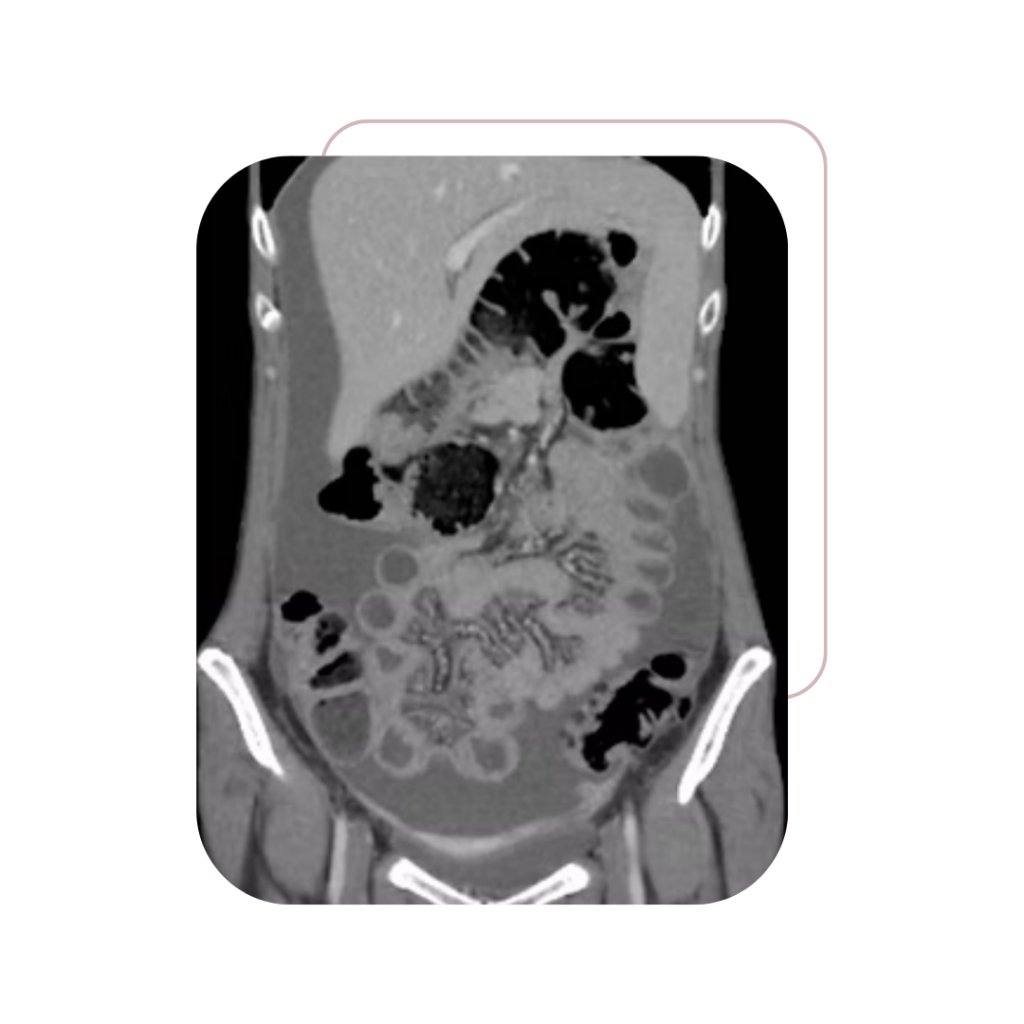

A Dra. Jacqueline Menezes dedica sua carreira ao tratamento e à preservação da saúde da mulher, com foco em cirurgias oncológicas ginecológicas seguras e minimamente invasivas.

Carcinomatose

Peritoneal

Massas Pélvicas

e Abdominais